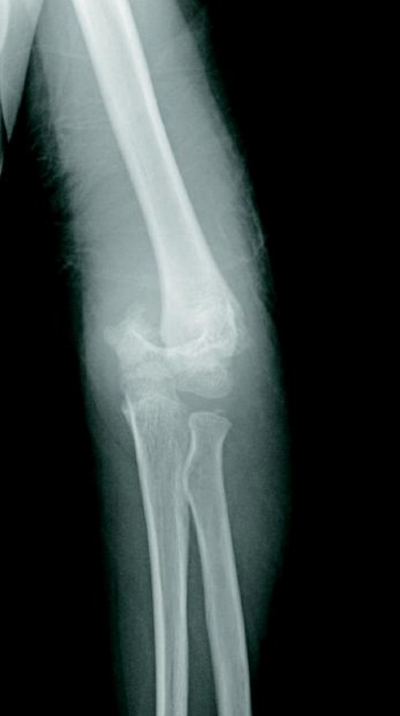

9歳の男児。左肘痛を主訴に母親とともに来院した。自転車乗車中に転倒し、左手をついて受傷した。左肘関節エックス線写真を別に示す。徒手整復を行う準備をしていたところ、左前腕部にも疼痛が出現し、左手指の自動運動が不能となった。